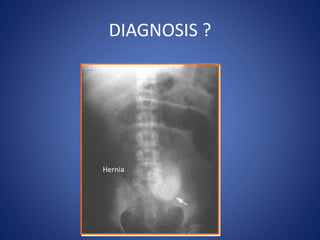

DIAGNOSIS ?

Hernia

Paralytic Ileus